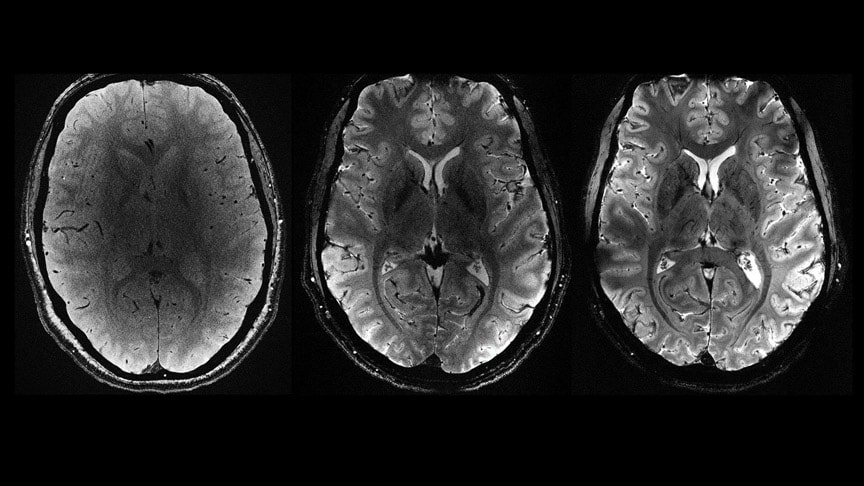

İngiltere merkezli araştırmacılar, 40-59 yaş arası 600’den fazla yetişkinle görüştü. Katılımcıların geçmişte travmatik beyin hasarı öyküsü olup olmadığı, manyetik rezonans görüntüleme (MRI) ile analiz edildi ve biliş, uyku, depresyon, yürüme ve kalp hastalığı riskleri değerlendirildi.

Erkeklerin neredeyse yarısı, kadınların ise yaklaşık %30’u en az bir beyin sarsıntısı geçirmişti. MRI’lar, beyin sarsıntısı öyküsü olanlarda beyin kan damarlarında değişikliklerin olduğunu gösterdi. Beyin sarsıntılarının uyku sorunları, yürüme bozuklukları, depresyon belirtileri ve hafif hafıza sorunlarıyla bağlantılı olduğu ortaya çıktı.